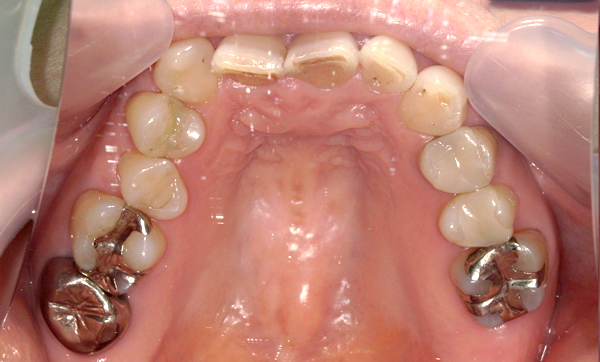

症例_016 上下顎の部分矯正

治療期間:8ヶ月金額:48万円+税50代女性八重歯捻転歯前歯のガタガタ